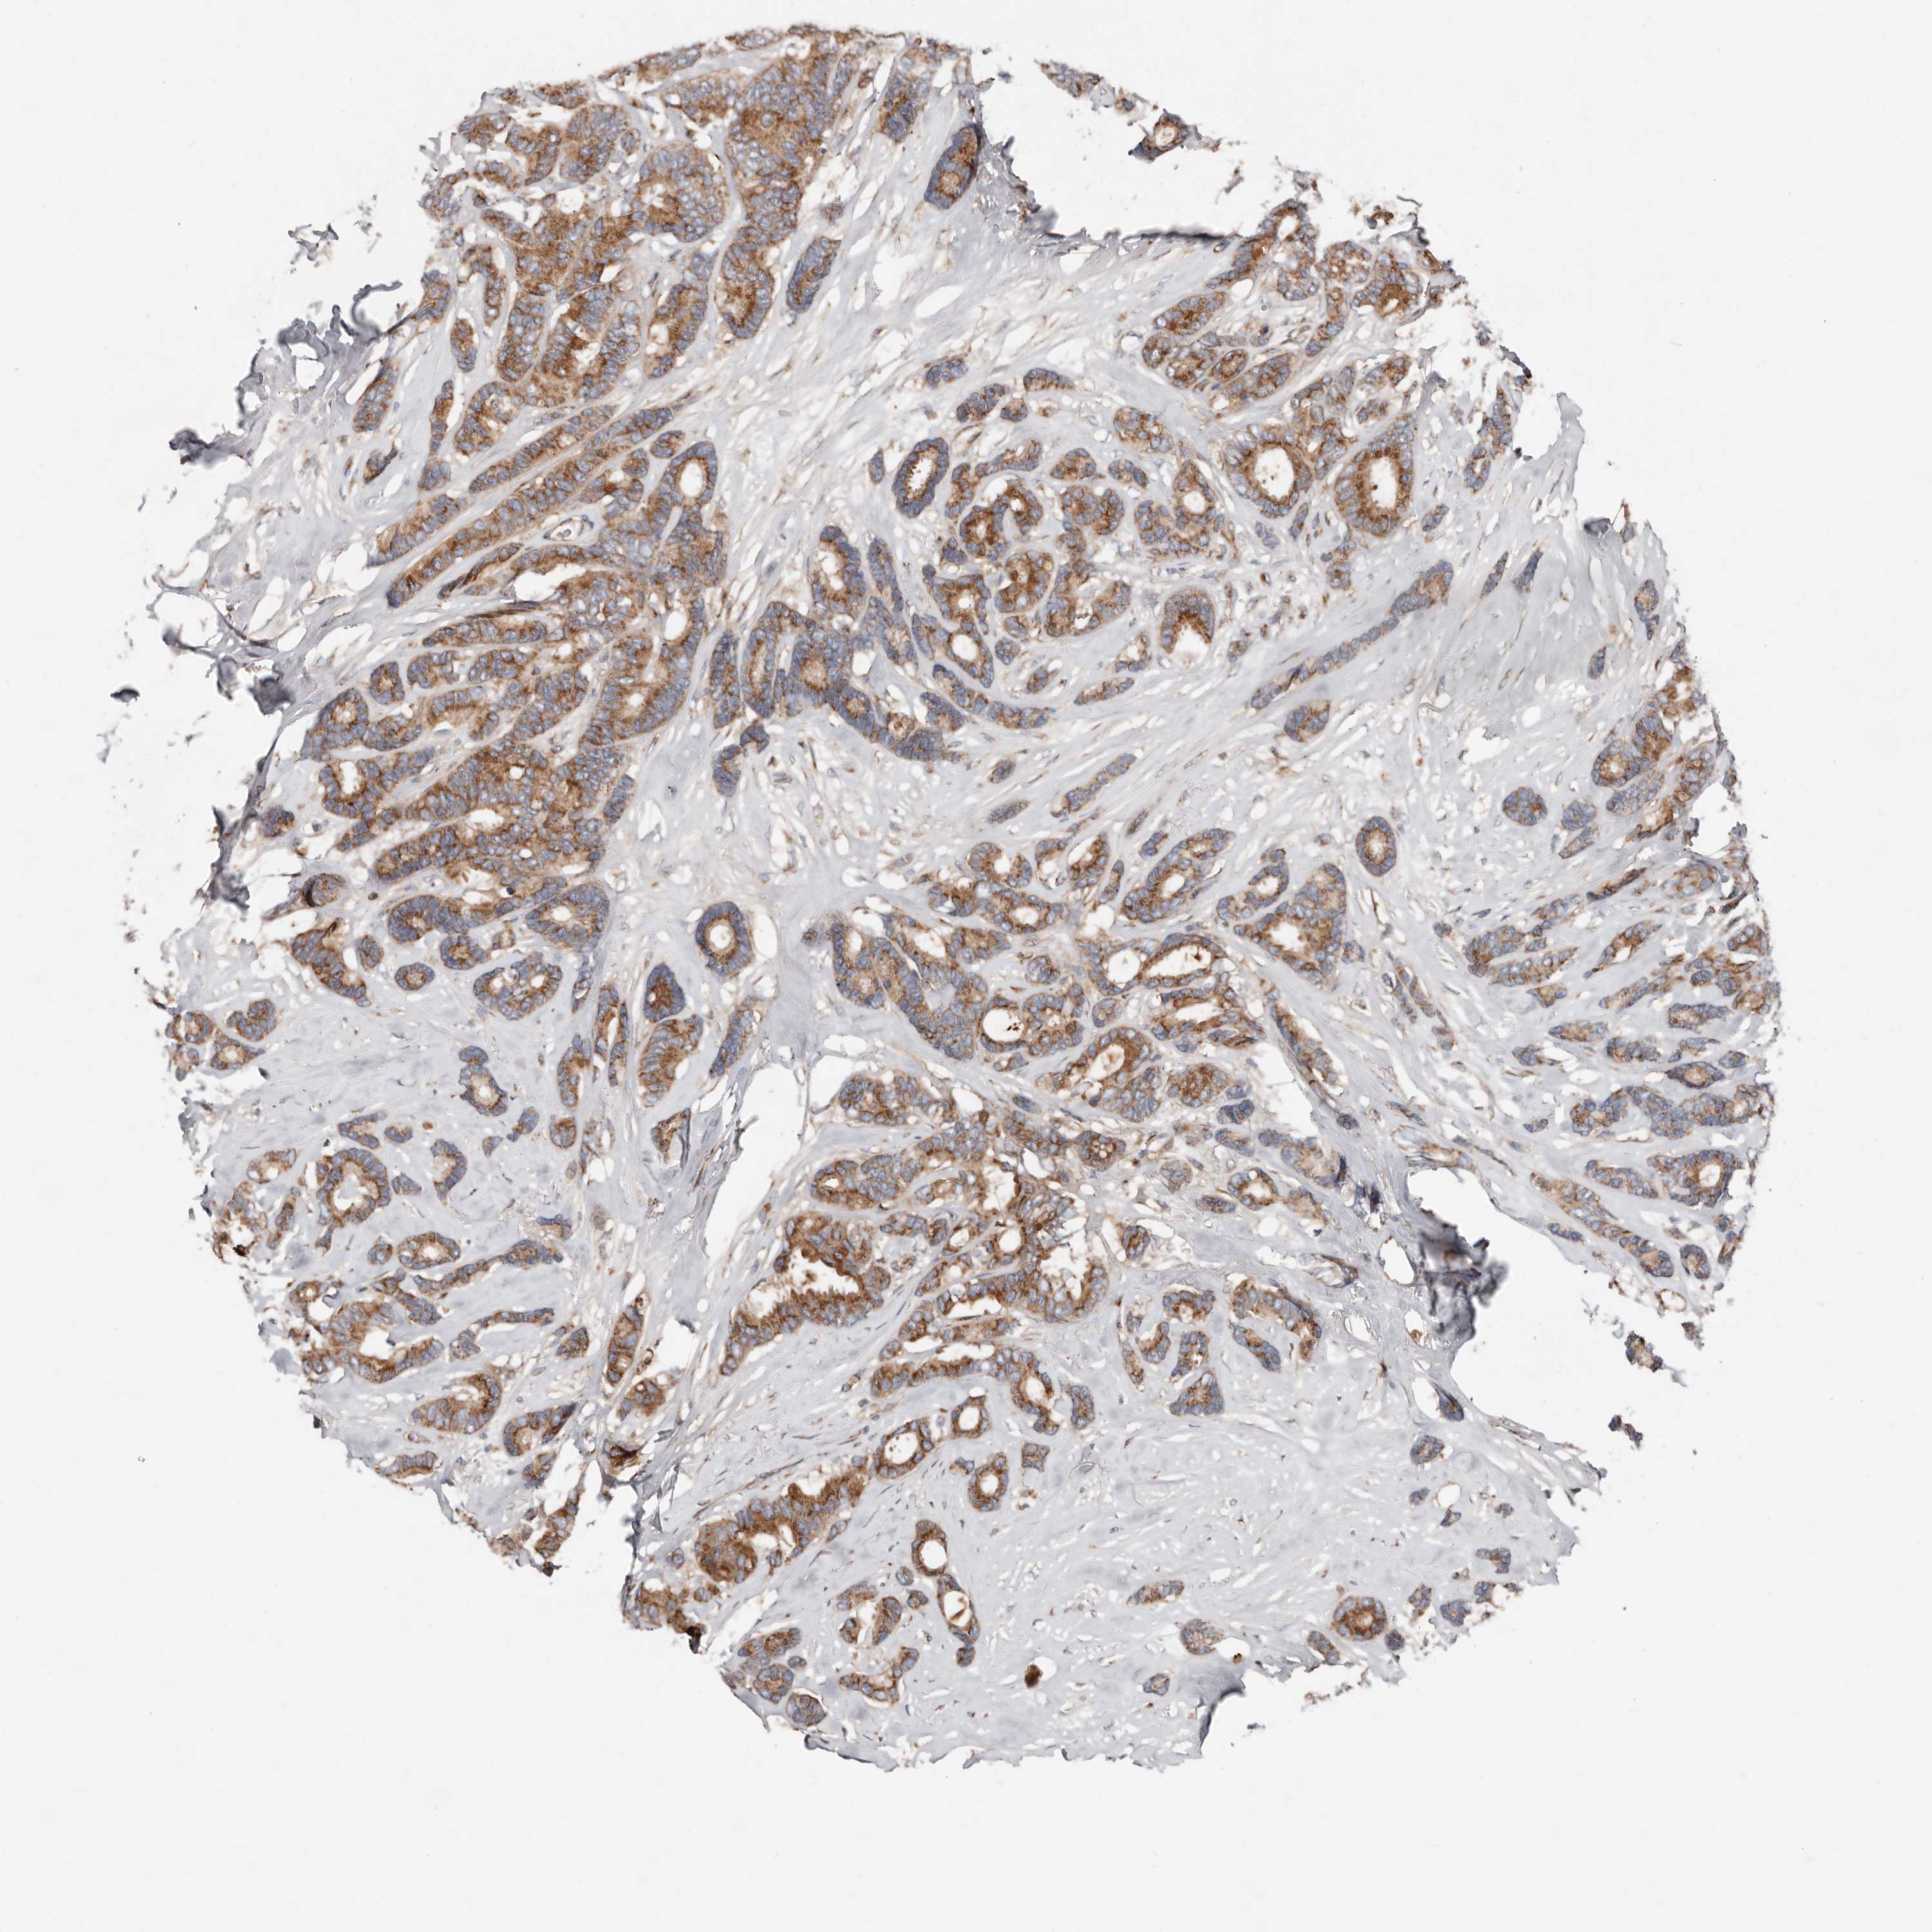

CANCER BREAST CANCER Show tissue menu

BRCA TCGA BRCA VALIDATION PROTEIN EXPRESSION